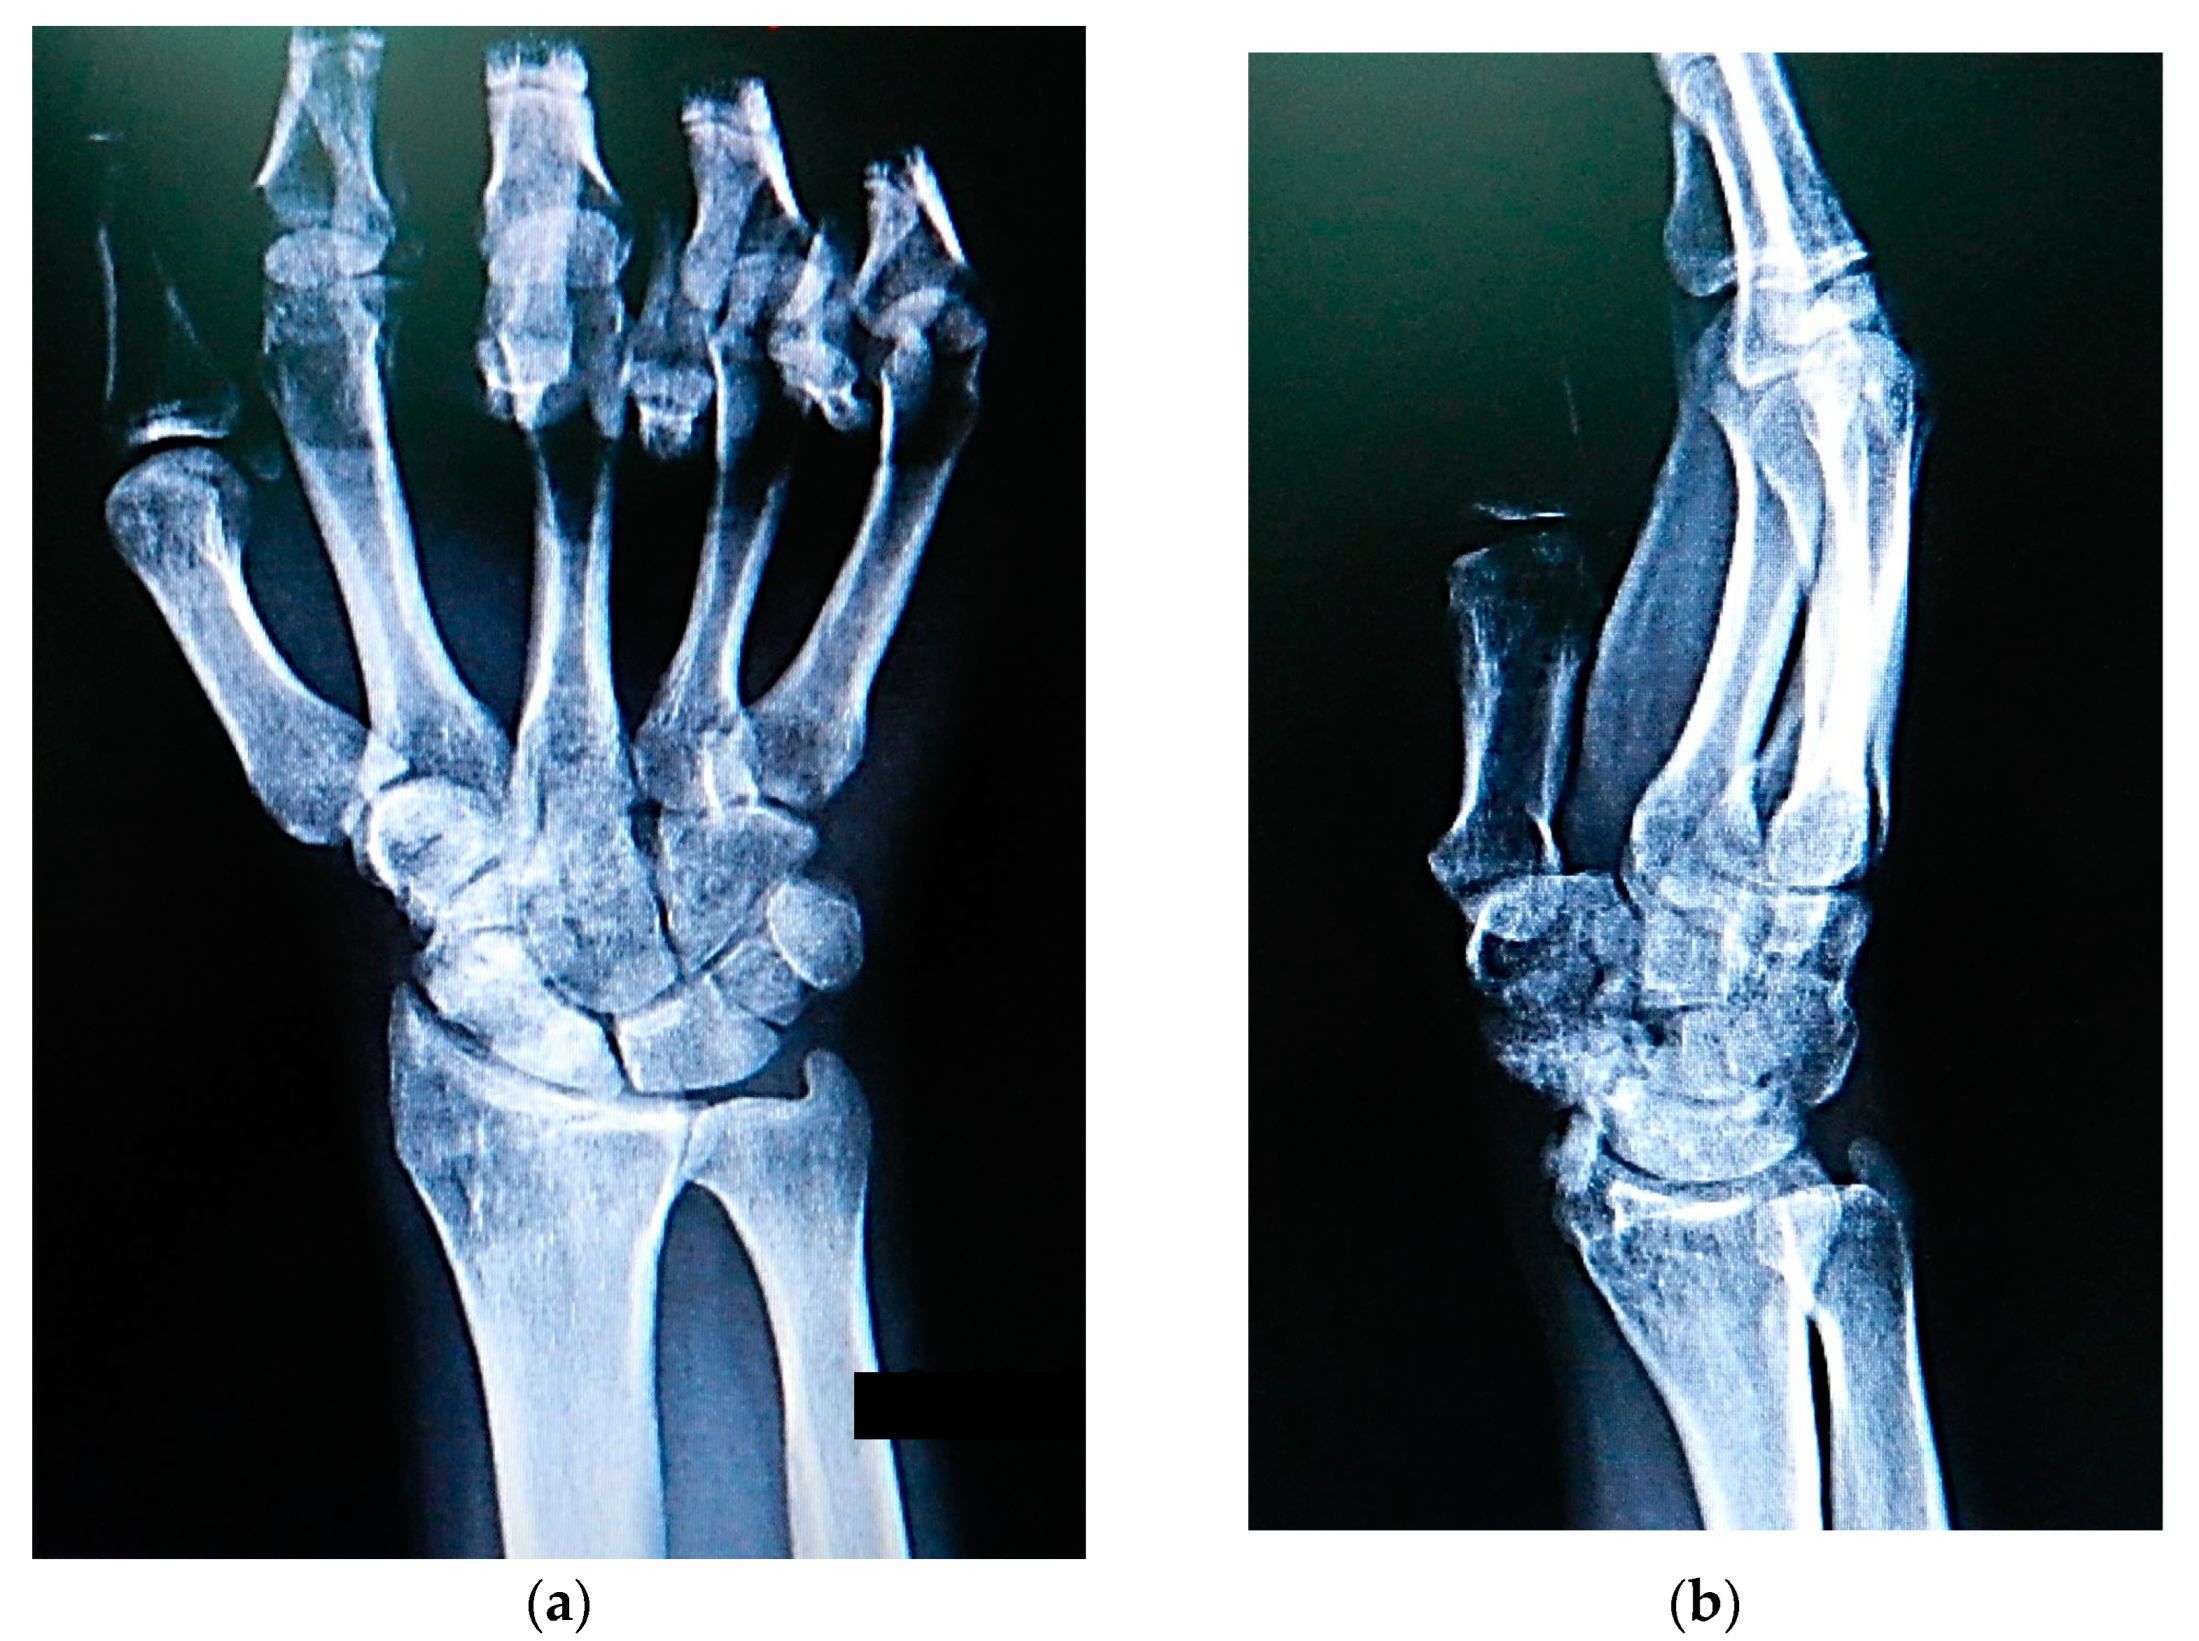

The most typical clinical sign of scaphoid nonunion is diminished wrist mobility [26], and one of the therapeutic goals is to increase the range of wrist motion. Research has suggested that an anterior approach for treating scaphoid nonunion results in the smallest loss of extension and flexion arcs [27]. However, other studies have shown that patients who undergo treatment with a PQPBG experience postoperative limitations in wrist motion, which are likely due to the muscle leash being sutured across the joint [28]. In our study, although flexion, ulnar, and radial deviations improved, we observed further postoperative limitations of restricted wrist extension, which contrasts with the findings reported by other studies [22,23,24] that reported postoperative improvements in all wrist movements, including extension. Limitations in one direction of motion and improvements in the other motions suggest that the limitation is not due to prolonged postoperative immobilization. We believe that the presence of the muscular leash crossing the joint volar and its possible shortening and stiffening over time, as revealed by radiologic calcification (Figure 6), may be the cause of this limitation.

Figure 6. (a)Posteroanterior and (b) lateral X-rays revealing complete bony union of the scaphoid nonunion and calcification of the pronator quadratus muscle at 6th month postoperatively.